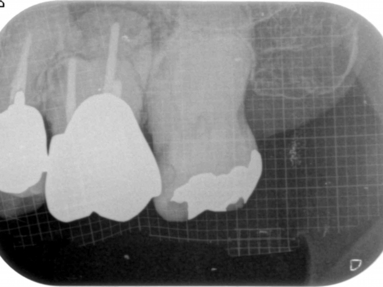

清潔な無菌的な根管の清掃が終了したら、緊密に根管充塡を行います。レントゲンで白く写る部分です。

根管治療の最後の処置です。根管の解剖学的な形態、彎曲度合い等によって数種類の根管充塡システムを当院では使い分けています。

- 前歯の違和感を主訴に来院した症例(写真をクリックして下さい)

- 歯内療法の不備から上顎洞にまで炎症が波及してしまった症例

初診時のレントゲン写真

写真の右から2本目の歯の違和感でいらっしゃいました。